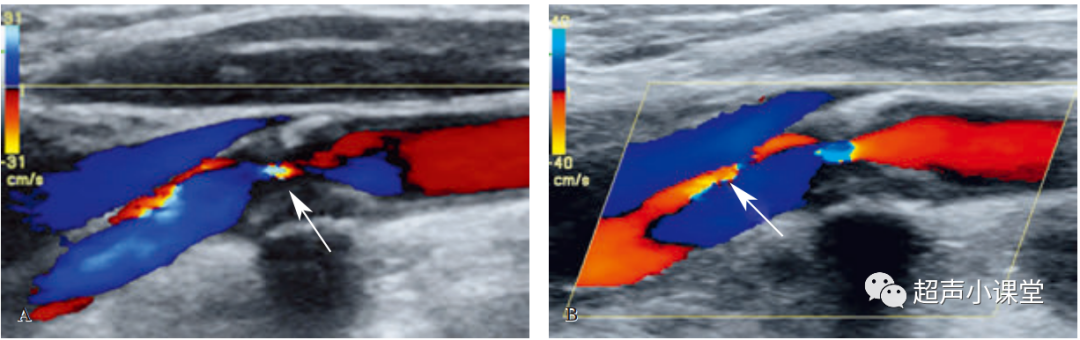

(二)狭窄即后段血流紊乱

检测到狭窄后区域内血流紊乱也是诊断狭窄重要的参考,表现为频谱波形的边界粗糙或者参差不齐,有时会出现涡流,检测到正向与反向波同时存在,一般存在于狭窄处的后1cm范围内.

如下图所示

一般重度狭窄不会存在于正常血管,如果发现,应该寻找附近狭窄的部位及其他血管病变.,尤其是当斑块较大时声影造成狭窄处显示不清时,发现重度紊乱血流应该高度重视.